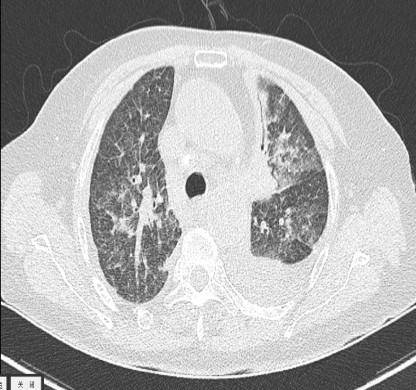

肺韦格氏肉芽肿ct征象大盘点!

图片尺寸504x312